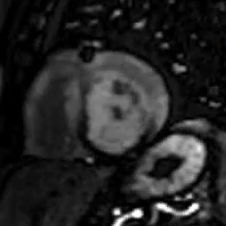

Η μαγνητική τομογραφία καρδιάς προσφέρει τη δυνατότητα λήψης υψηλής ανάλυσης εικόνων της καρδιάς, επιτρέποντας έτσι την λεπτομερή μελέτη των δομών και της λειτουργίας της. Εκτός από την υπεροχή της μεθόδου έναντι άλλων στην ποιότητα και καθαρότητα της εικόνας χωρίς περιορισμούς από το σωματότυπο ή τη χρήση ιονίζουσας ακτινοβολίας, η μέθοδος αυτή είναι η μοναδική που μπορεί να δώσει πληροφορίες για το μυοκαρδιακό ιστό και να απεικονίσει τη μυοκαρδιακή βλάβη (φλεγμονή, ίνωση, νέκρωση), καθιστώντας τη απαραίτητο εργαλείο σε πλήθος καρδιακών νοσημάτων και καταστάσεων. Ενδεικτικά παρακάτω γίνεται αναφορά σε κάποιες.